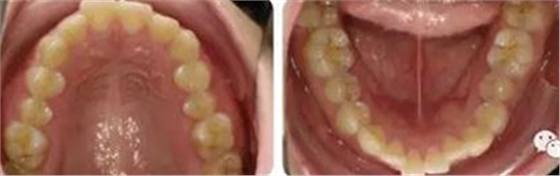

女性,24歲,主訴牙列不齊,面型突。

開唇露齒,閉口時(shí)唇肌緊張,反笑線,突面型。

上下牙列輕度擁擠,牙弓偏尖圓形;前牙深覆合深覆蓋;雙側(cè)磨牙尖牙偏遠(yuǎn)中關(guān)系。

安氏Ⅱ類、骨性Ⅱ類錯(cuò)頜畸形。